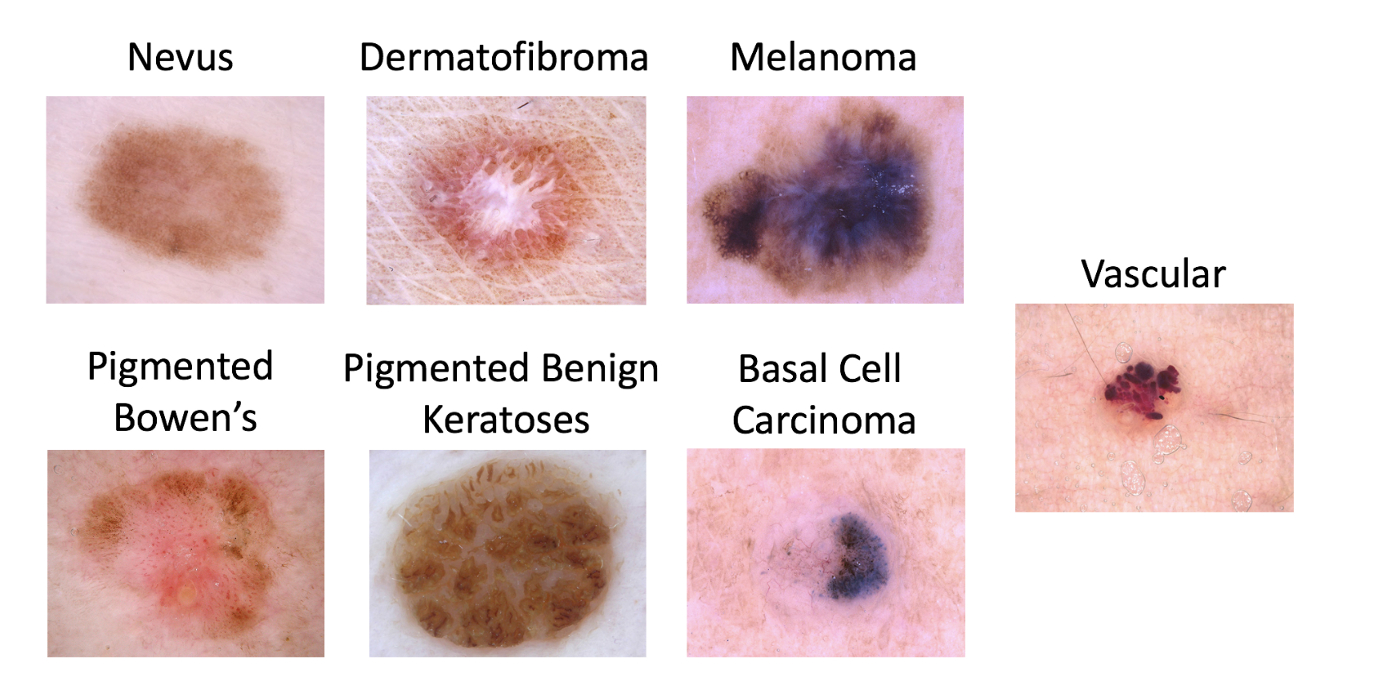

(The full list of lesion types types to classify in the ISIC dataset. We’ll be focusing on Melanoma vs. non-Melanoma)

(The full list of lesion types types to classify in the ISIC dataset. We’ll be focusing on Melanoma vs. non-Melanoma)